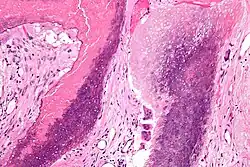

Pilomatrixome

Le pilomatrixome (ou "pilomatricome", ou "épithéliome calcifié de Malherbe") est une tumeur bénigne cutanée d'origine annexielle folliculaire. La tumeur survient surtout chez les enfants et les adolescents avec prédominence féminine et se localise au niveau de la tête et du cou[1]. Cliniquement on trouvera fréquemment un nodule sous-cutané unique, de taille inférieure à 3 cm et asymptomatique (parfois douloureux)[2].